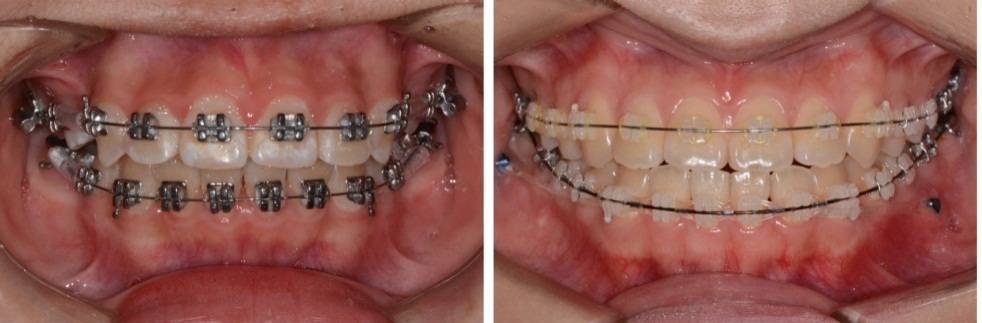

唇侧矫治器根据不同材料,主要分为金属矫治器和陶瓷矫治器;根据弓丝安放方式,又可分为自锁和非自锁矫治器两大类。金属非自锁矫治器最普通,每颗牙都需要通过结扎丝来固定弓丝,较显眼;而陶瓷非自锁矫治器较金属更为美观,但也需要结扎丝结扎;金属自锁矫治器能够通过矫治器上的“盖子”锁住弓丝,不需要结扎丝结扎,因而更舒适,医生操作更简便,排齐速度也略快;陶瓷自锁矫治器则较为美观,且不需要结扎丝结扎来固定弓丝,同时满足美观、舒适的特点。

(摘自“第三章第三节 牙套的选择”)

金属非自锁矫治器(左)与陶瓷非自锁矫治器(右)

金属自锁矫治器(左)与陶瓷自锁矫治器(右)